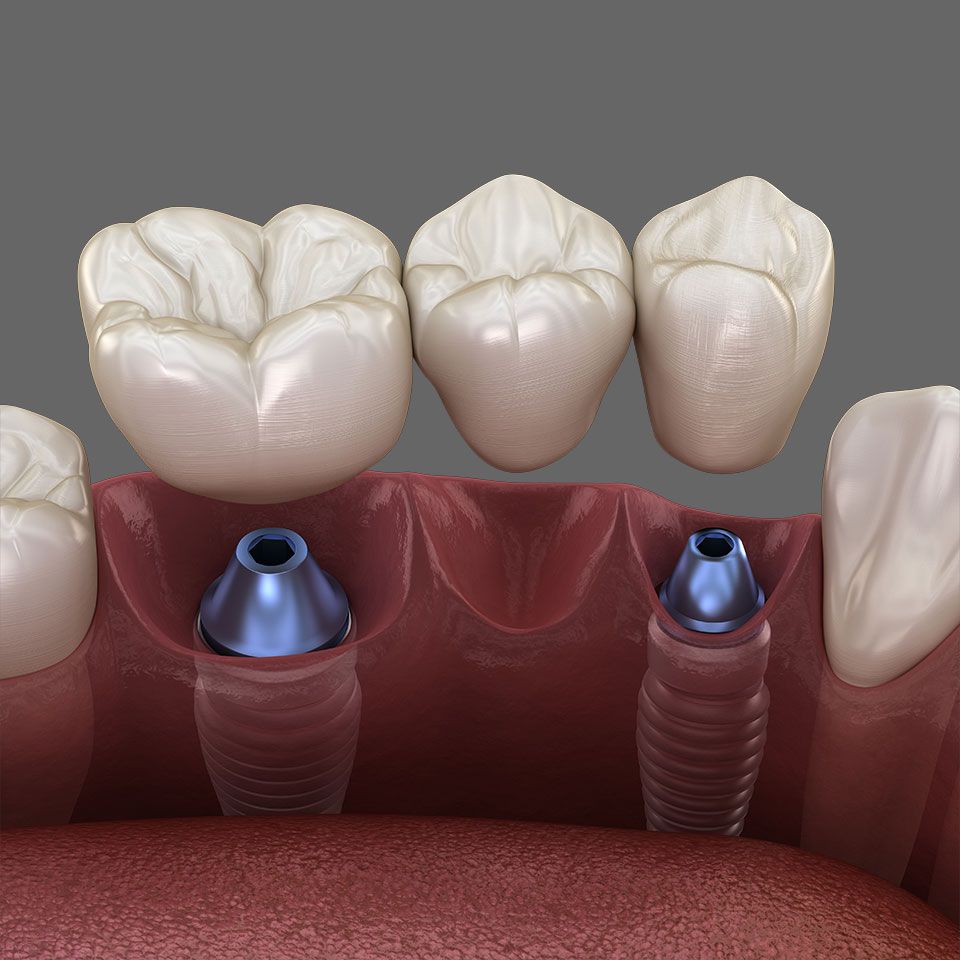

Um einzelne Zähne zu ersetzen und Lücken zu schließen, sind Implantate heute die erste Wahl. Der Kieferknochen bleibt intakt und die Nachbarzähne werden geschont.

Diese künstlichen Zahnwurzeln sind zumeist aus Titan – einem gut verträglichen (biokompatiblen) Material. Sie werden in den Kieferknochen eingesetzt, wo sie mit dem Knochen fest verwachsen. So können sie einer Einzelkrone, Brücke oder Zahnprothese stabilen Halt verleihen.

Implantate schonen gesunde Zahnsubstanz: Anders als bei Brücken, bei denen eventuell gesunde Nachbarzähne abgeschliffen werden müssen, bleibt die Zahnsubstanz der übrigen Zähne bei einer Implantation komplett erhalten.